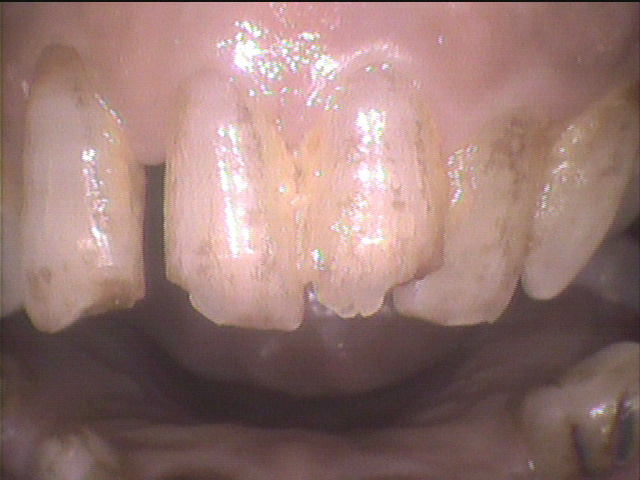

◎クリーニング前

下の前歯の表側のお写真です。

歯石が歯間部に付いていて、着色汚れもありました。